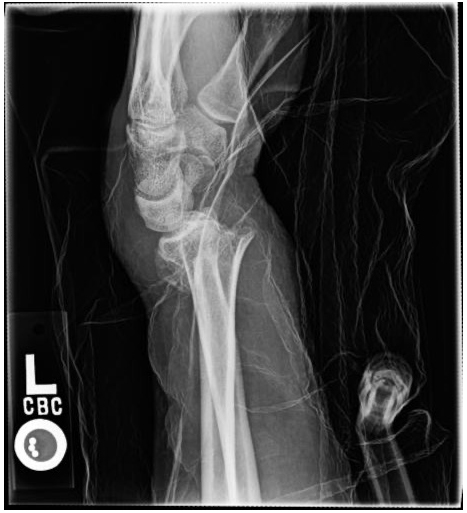

X-rays will be used to confirm the diagnosis. Fortunately, many of these fractures can be treated without surgery. Sometimes, the best thing is to push the fracture back into a better position and then hold it there with a cast. However, there are occasions where surgery is the best option. Surgery allows for the bones to be held in a better position more securely. With surgery, the bones can be held in place with pins, plates, and screws, and sometimes a combination of all of these. No matter the treatment, these fractures usually require at least 6 weeks to heal before it is ok to begin using the hand and wrist without restriction, but it often takes months before the pain and the stiffness fully resolve.

60-year-old female without other medical problems fell and landed primarily on her left hand and wrist. She had immediate pain and deformity at the wrist. She went to the emergency room where x-rays were performed showing her injury – a distal radius fracture. An attempt was made at improving the fracture position by the emergency room doctors and she was splinted. She was then referred to my clinic. She was seen soon afterwards. It was noted on new x-rays that the broken bone was in a less than ideal position. After a thorough discussion of the patient’s goals and concerns, surgery was felt to be the best option for her. Surgery was performed one week after her initial injury under general anesthesia. She was allowed to begin moving her wrist after her first post-operative visit 10 days after surgery and begin full weight bearing on the hand and wrist just under 6 weeks after surgery. She now has full function.